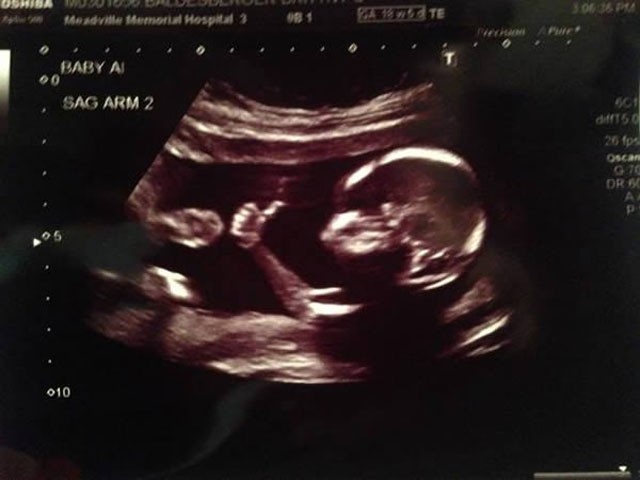

Eli dinozor gibi duran bebek